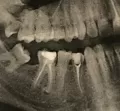

Сегодня на снимке увидели, что возле корня какое-то черное пятно. Сказали нужно вырывать зуб, но я молодой парень, не хочется лишиться зуба в таком раннем возрасте.

"Чёрное пятно" в области верхушки корня может говорить, о воспалительном процессе ("чёрное пятно" является участком разряжения костной ткани, в зависимости от размера данного участка, это может быть периодонтит, гранулема или киста).

Оценить Вашу ситуацию без рентгеновского снимка сложно.